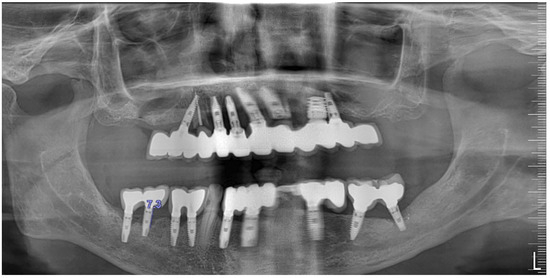

An 80-year-old male patient presented at the private dental office with severe mandibular pain, swelling, and mobility of a dental prosthesis retained by implants. The chief complaint was the lack of stability and mobility in mandible rehabilitation, with the symptoms already described. The medical history included controlled hypertension, hypercholesterolemia, anticoagulant therapy, and a history of heavy tobacco use, which ceased 15 years prior to the oral rehabilitation. The clinical examination revealed inadequate oral hygiene, extensive fixed-prosthesis and dental implant mobility, with PDs exceeding 10 mm; significant BoP was found, and severe vertical bone loss was radiographically confirmed around implant #33, #36, #37, #41, #43, #44, and #47 (Figure 16).

Figure 16. Panoramic radiographic view (a) and cone-beam computed tomography (CBCT) (b), revealing bone loss at baseline at tooth #41, respectively, 8.5 mm and 9.0 mm (red arrows).